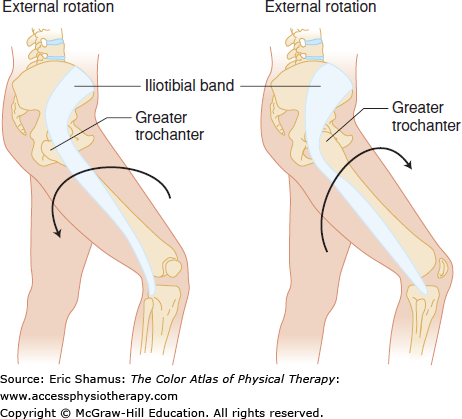

Answer with rationale: A. Ober Test, Noble Compression Test, Creak Test. All three of these test are considered positive if pain or crepitus is reproduced. Pain reproduced through these tests supports a diagnosis of iliotibial band syndrome.